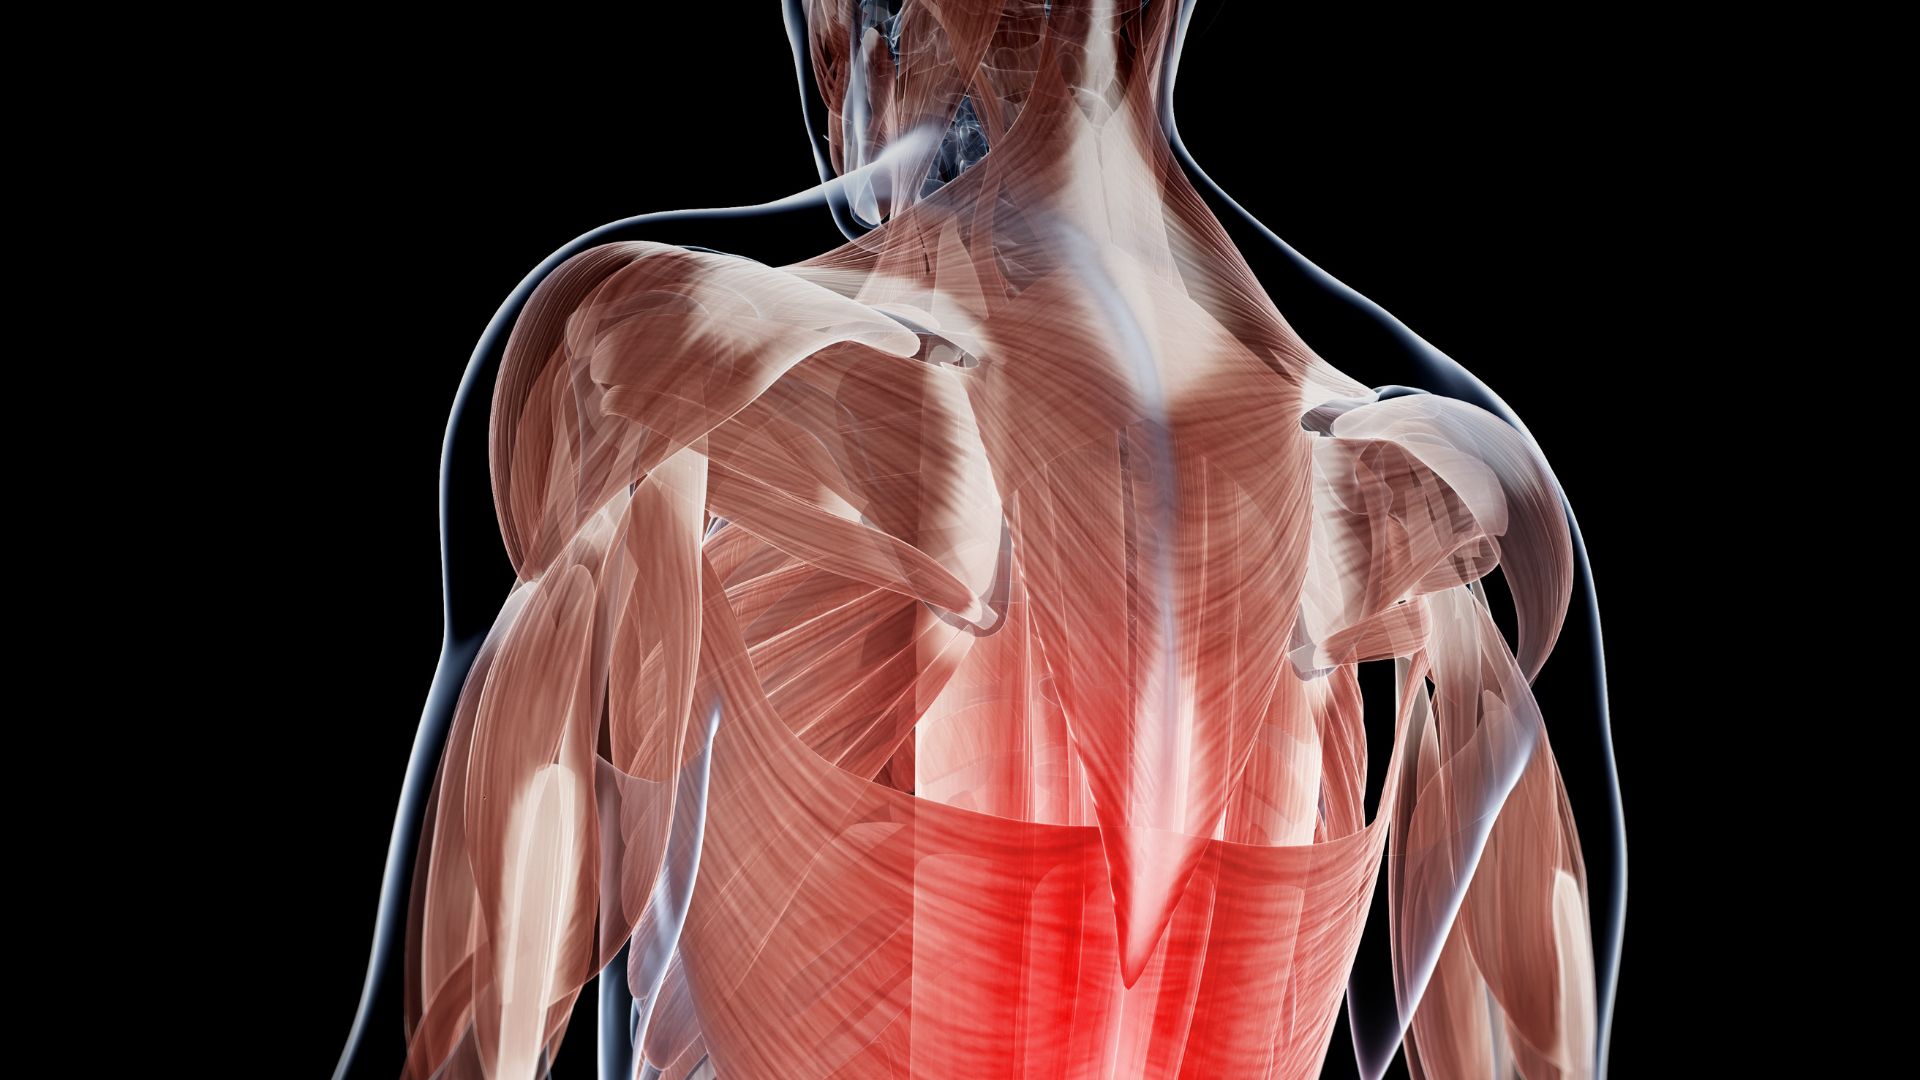

Leia também: Práticas diárias que podem te ajudar a aliviar a dor nas costas